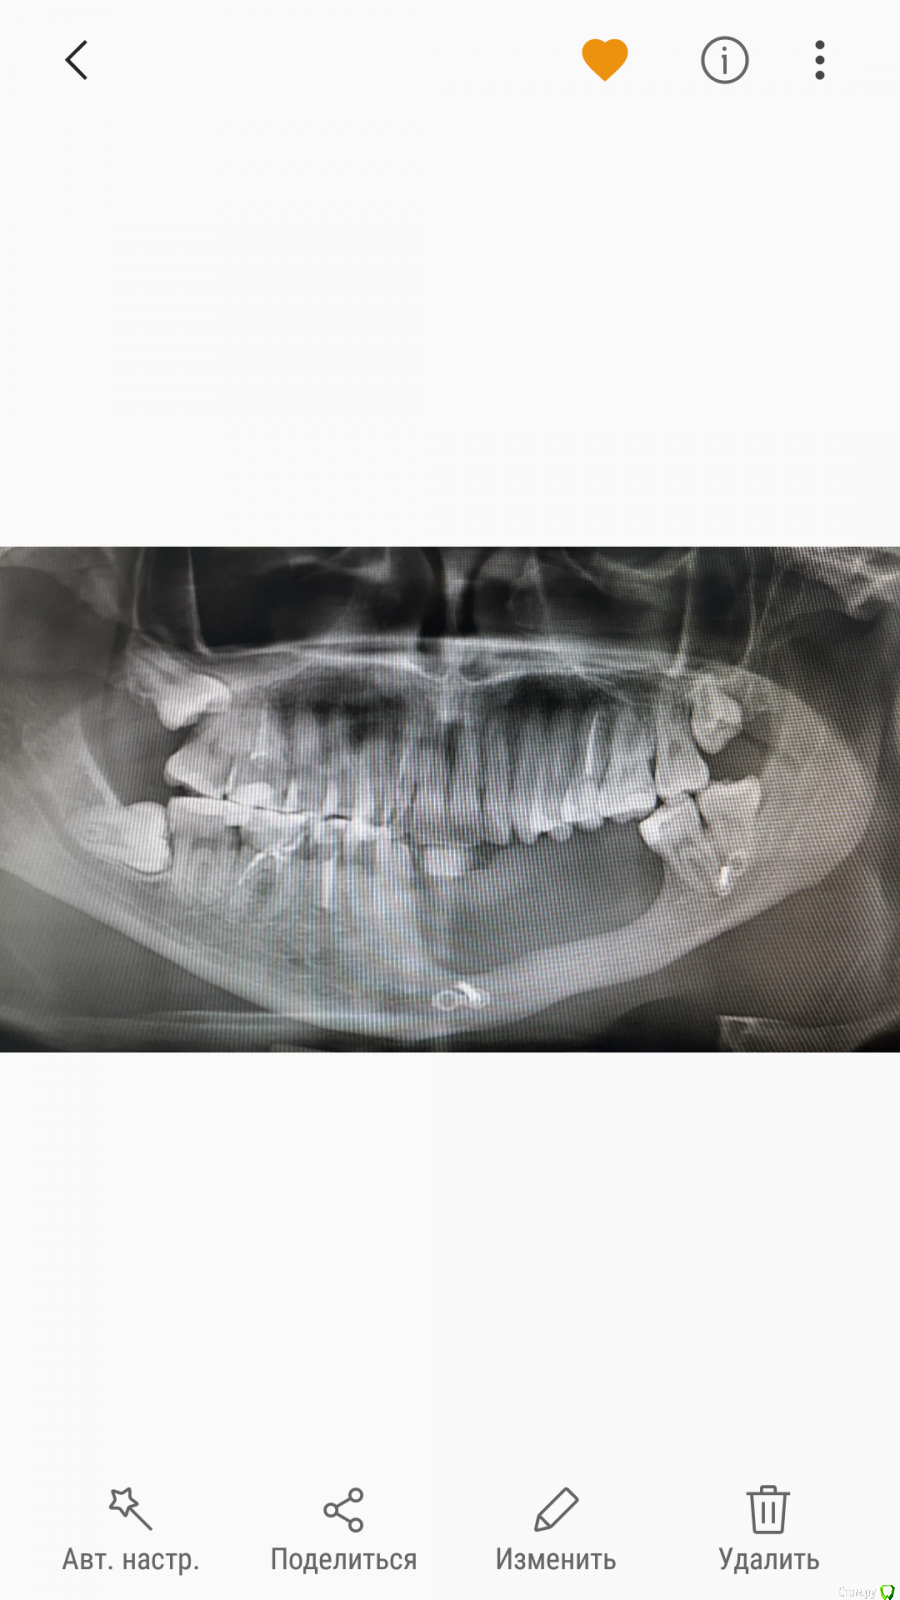

martynyukm Опубликовано 14 марта, 2018 Поделиться Опубликовано 14 марта, 2018 Здравствуйте,уважаемые знатоки.В кратце живу не в России и посещение стоматолага обходится в копеечку. На снимке вижу что 2 з.мудрости растут вбок и подпирают уже соседей. Местные врачи настаивают на удалении тк испортятся соседние зубы. По приезду в Россию местный врач сказал,что особо не видит у меня мотивации для удаления.тк ничего не беспокоит. Так же описал возможные осложнения,что 2 недель моих каникул в России может не хватить на лечение. Вопрос:стоит ли удалять "без причины" ,просто чтобы "потом не беспокоили"? Ссылка на комментарий

martynyukm Опубликовано 15 марта, 2018 Автор Поделиться Опубликовано 15 марта, 2018 (изменено) Снимок Изменено 15 марта, 2018 пользователем martynyukm Ссылка на комментарий

Irouil Опубликовано 15 марта, 2018 Поделиться Опубликовано 15 марта, 2018 Да, удалять нужно все 1 Ссылка на комментарий

Bier Опубликовано 15 марта, 2018 Поделиться Опубликовано 15 марта, 2018 я бы удалил Ссылка на комментарий

колесников Опубликовано 16 марта, 2018 Поделиться Опубликовано 16 марта, 2018 Расскажите предысторию адентии на нижней челюсти. 1 Ссылка на комментарий

martynyukm Опубликовано 17 марта, 2018 Автор Поделиться Опубликовано 17 марта, 2018 Расскажите предысторию адентии на нижней челюсти.Была то ли остеоблостома,то ли кластома забыла название. Вырезали кусок кости с зубами,позже нарастили кость из ребра,потом еще нарастили из бедра. Вот так в Москве делали. Ношу зуб.протез Ссылка на комментарий

red_butler Опубликовано 18 марта, 2018 Поделиться Опубликовано 18 марта, 2018 Да, удалять нужно все я бы удалил+ 1 Ссылка на комментарий